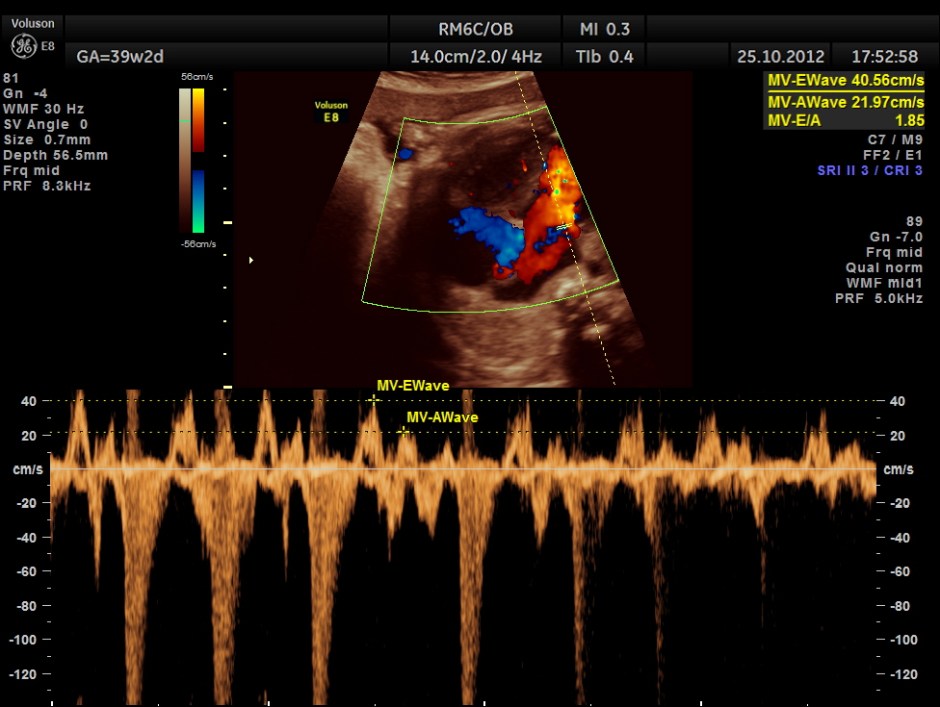

THIS FETUS HAD SEVERE FETAL ANEMIA WITH CARDIAC FAILURE LEADING TO CARDIOMEGALY WITH MITRAL, TRICUSPID AND PULMONARY REGURGITATION .NO OTHER OBVIOUS CARDIAC ANOMALY WAS MADE OUT . THE VENO ATRIAL , ATRIO VENTRICULAR AND VENTRICULO ARTERIAL CONCORDANCE APPEARED TO BE NORMAL; NO SEPTAL DEFECT WAS MADE OUT.